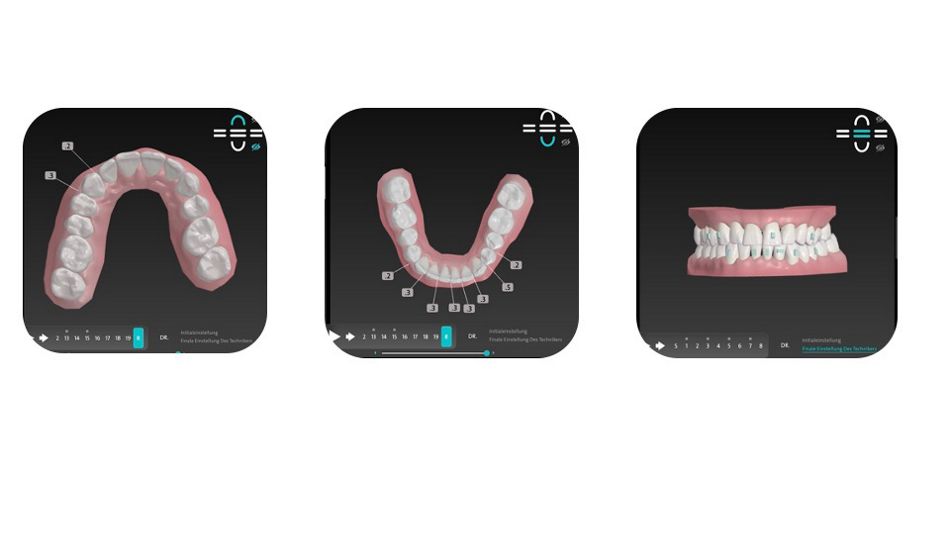

Zunächst einmal wurde der Patient mit dem TRIOS 4 Scanner intraoral gescannt. Es wurden 8 kieferorthopädische Fotos aufgenommen. Diese Daten wurden unter kieferorthopädischen, funktionalen und ästhetischen Aspekten analysiert [1,2,3,4] und in das ClearCorrect Portal hochgeladen, wo eine Fallplanung wenige Tage später vorgeschlagen wurde.

Das Hauptziel war es, die Oberkieferfront, die aufgrund des tertiären Engstandes retrudiert war, wieder aufzurichten, sowie durch die Retrusion und Intrusion der Unterkieferfront, soviel Overjet zu schaffen, dass der Unterkiefer durch Autorotation in eine bequemere Position gelangen kann. Gleichzeitig wurde durch bukkalen Wurzeltorque der oberen Prämolaren, der Oberkiefer leicht expandiert, um einen ästhetischen Bukkalkorridor zu erlangen und dem Unterkiefer etwas mehr Platz in der Transversalen zu gewähren [4].

Kieferorthopädisches Vorgehen

Die ersten Aligner wurden eingesetzt. Es waren insgesamt 19 Aligner Sets für die erste Phase der Behandlung vorgesehen. ASR wurde in Höhe von 2,4mm im Unterkiefer appliziert, um genug Overjet durch Retrusion der Unterkieferfront zu gewährleisten und gleichzeitig den Frontzahnengstand zu beheben. Der Oberkiefer benötigte nicht mehr als 0,5mm ASR. Es wurden vertikale Attachments auf 14, 13, 21, 24, 25, 33, 31, 32 angebracht, um Rotationen und bukkalen Wurzeltorque der Incisivi und Prämolaren zu ermöglichen, wodurch der Zahnbogen wieder als Ganzes aufgerichtet werden sollte. Es wurde nur ein horizontales Attachment auf 31 appliziert, um dessen Intrusion zu erleichtern.

Nach 19 Aligner Stufen, wurden alle bisherigen Attachments entfernt und für die Revision gescannt, um etwas mehr Overjet zu schaffen. Weitere 11 Aligner Sets wurden geplant und vom Patienten getragen. Um Zahn 11 körperlich besser bewegen zu können, wurde ein 3 x 1 mm horizontales Attachment angebracht. Weitere 0,9mm ASR wurden im Unterkiefer durchgeführt, um die Unterkieferfront weiter zu retrudieren. Im Oberkiefer wurde lediglich zwischen Zahn 11,21 0,3mm ASR appliziert, um das verbleibende schwarze Dreieck zu schließen. Die Revision sollte nie als Fehlversagen eingeordnet werden, sondern vielmehr als Möglichkeit ein hundertprozentiges kieferorthopädisches Ergebnis für den Behandler und Patienten zu erreichen.

Fallplanung vorher und nachher hinsichtlich der Envelope of Function

Fallplanung vorher und nachher bezüglich der inzisalen Inklination und der daraus resultierenden restriktiven Envelope of Function und dessen Korrektur.